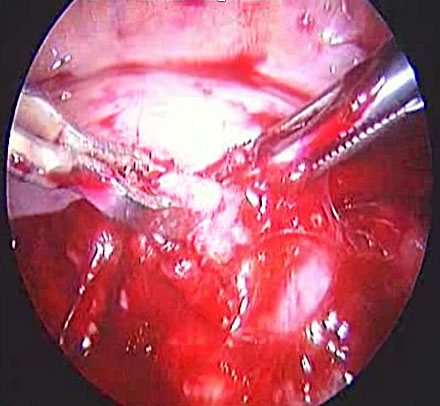

In the event of uterine artery bleeding during dissection, once identified, the laparoscopist should remain calm. CO₂ insufflation and suction at pressures below 300 mmHg help maintain pneumoperitoneum. The bleeding vessel should be carefully grasped with bipolar cautery forceps or another appropriate instrument (Figure 17) after adequate dissection. Occasionally, the presence of a gauze piece can help localize the bleeding source. It is important to avoid forcefully grasping the bleeding area, as the uterine artery lies above the ureter, which in turn is above the uterine vein. If the bleeding originates from the vein, bipolar cautery may inadvertently damage the ureter. Once hemostasis is achieved, hemostatic agents such as Surgicel may be applied, although they are often unnecessary.

(a) |

(b) |

(c) |

17

(a) Right uterine artery active bleeding after removal of the uterus. (b) Stabilizing the bleeder by atraumatic forceps with suction. (c) Stabilized tip of the vessel coagulated with bipolar cautery forceps.